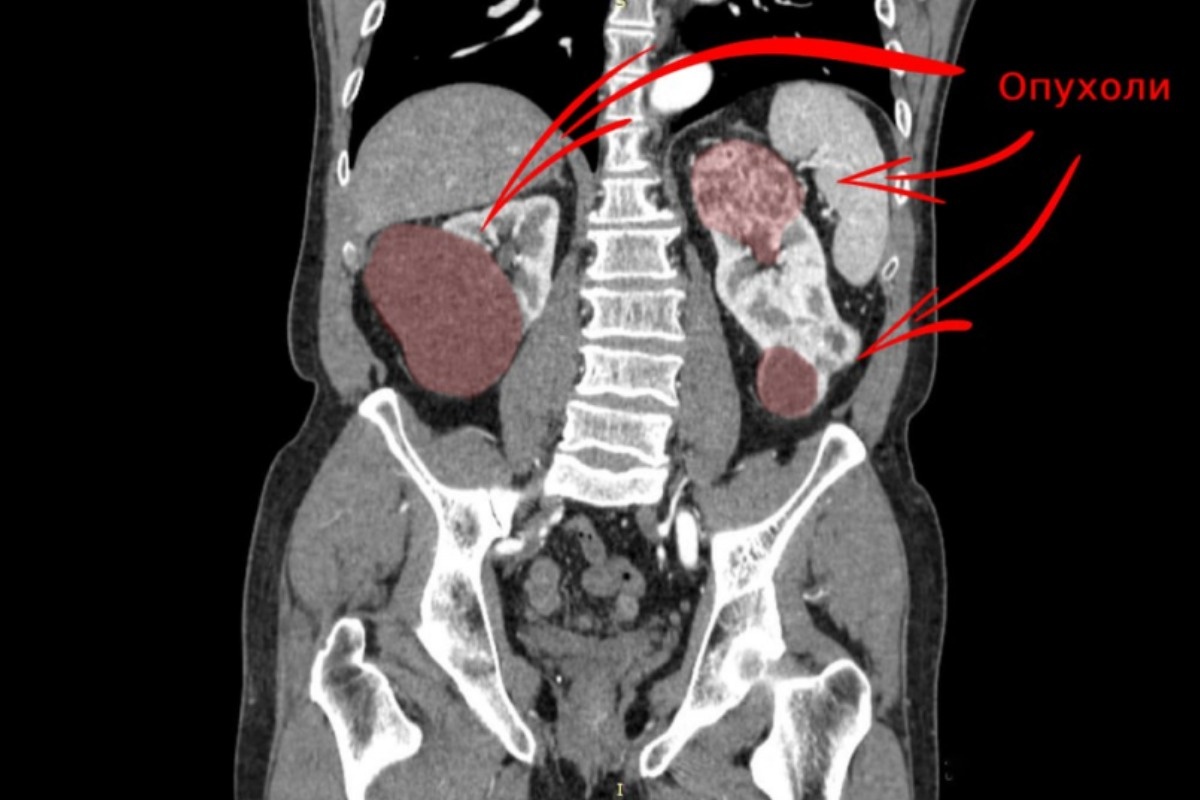

Врачи отделения онкоурологии Свердловского областного онкологического диспансера провели уникальное лечение пациента с редким видом синхронного рака, при котором злокачественные опухоли поразили обе почки. Об этом случае сообщили в минздраве региона. Такой диагноз встречается лишь в 2-6% случаев онкологических заболеваний почек. Целью врачей было сохранить жизнь пациента и дать ему шанс избежать постоянного гемодиализа. Опухоль у мужчины была заподозрена на ранней стадии во время планового медосмотра врачом первичного звена. На углублённом обследовании в онкодиспансере обнаружили, что правую почку поражала опухоль диаметром более 6 см, захватившая около половины паренхимы (элемента почечной ткани), поэтому почку пришлось удалить. Левая почка также была поражена новообразованиями. Врачи провели вторую сложную операцию — удалили опухоли в верхнем и нижнем сегментах левой почки суммарным размером 12 см. Однако при этом удалось сохранить 70% почечной ткани. Хирург Александр Орлов отметил,

Опухоль у мужчины была заподозрена на ранней стадии во время планового медосмотра врачом первичного звена. На углублённом обследовании в онкодиспансере обнаружили, что правую почку поражала опухоль диаметром более 6 см, захватившая около половины паренхимы (элемента почечной ткани), поэтому почку пришлось удалить. Левая почка также была поражена новообразованиями.

Врачи провели вторую сложную операцию — удалили опухоли в верхнем и нижнем сегментах левой почки суммарным размером 12 см. Однако при этом удалось сохранить 70% почечной ткани. Хирург Александр Орлов отметил, что операция прошла с короткой ишемией (ограничением притока крови) всего в 12 минут, что минимизировало риск вреда органу. Пациент выписан из стационара и находится под наблюдением нефрологов с сохранённой функцией почек и возможностью вернуться к полноценной жизни без необходимости в гемодиализе.